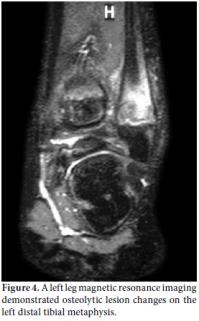

A 10-year-old boy was referred to the Pediatric Rheumatology Unit at the University Hospital Federal University of Pernambuco, Recife in 2008 with a fiveyear history of intermittent pain in his left clavicle, right hip, ankles, and dorsal spine. In 2006, he was admitted to the Pediatric Unit complaining of back pain, fever, and a mass over his left clavicle. Blood tests showed a C-reactive protein (CRP) level of 24 mg/dl and an erythrocyte sedimentation rate (ESR) of 39 mm/h. A chest X-ray confirmed the mass over his left clavicle (Figure 1). Septic osteomyelitis was diagnosed, although his blood and bone cultures were negative. A course of an empirical antibiotic (cephalothin) and NSAIDs was prescribed. He was later referred (after one year) to the Orthopedic Unit where a thoracic computed tomography (CT) scan showed the volume of the left clavicle had increased due to an area of hyperostosis mixed with osteolysis. Hence, the antibiotic was changed to ciprofloxacin for three months. As there was no improvement, he was referred to the Pediatric Rheumatology Unit, where a tuberculin test and ANA were negative. A bone scan showed an increased technetium-99m (99mTc) radioisotope uptake at the left clavicle, ankle, sacroiliac joints, and T8 thoracic disc (Figure 2). Magnetic resonance imaging (MRI) demonstrated multiple inflammatory lesions between the T7 and T9 disks (Figure 3) and in the left clavicle and left ankle (Figure 4), thus confirming the findings on the bone scan and thorax CT. The results of the histological analysis of a bone biopsy were compatible with aseptic chronic osteomyelitis (Figure 5). No infection was identified by lesion or blood culture, and no malignancy was detected by imaging; hence, the possibility of CRMO was raised. An aggressive treatment with NSAIDs, alendronate 70 mg/week, methotrexate 15 mg/week, and infliximab 5 mg/kg was initiated due to the severity of the case and the delay in diagnosis. After the third infusion of infliximab, the boy became free of pain. His ESR and CRP levels were normal, and a bone scan showed a tiny uptake at the left clavicle. It should be noted that the patient and his family gave their consent for any treatment provided at the Pediatric Rheumatology Unit.

An X-ray can show areas of osteolysis at the metaphysis and diaphysis as well as the sclerosis around it.[10,11] Bone scans (99mTc), CT, and MRIs can help in the diagnosis by determining the location for a bone biopsy and assessing the activity of the disease.[11] The X-ray and MRI images were of great importance in our case since they provided evidence of the osteolysis and bone enlargement lesions.[12,13] Vertebral compression is a rare radiographic finding, but an MRI revealed compressive lesions of the spine at T7-T9 along with scoliosis in our patient. His pain was lessened after he was treated with NSAIDs.